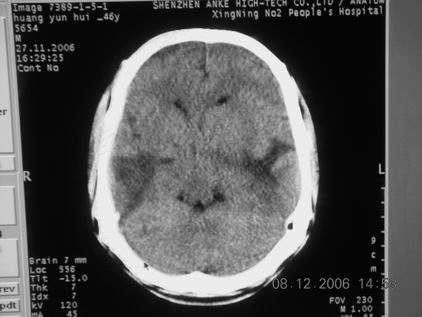

标题: CT11164:男,46岁,白血病患者,,大家看看. [打印本页]

标题: CT11164:男,46岁,白血病患者,,大家看看.

以前的片子,病史忘了,男,46岁,白血病患者,后来到中山二院诊断为

谁见过白血病中枢系统改变是怎么样的吗?

多发性脑脓肿?

白血病脑浸润。

支持白血病脑浸润.

1 多发脑脓肿可能性大.>2 白血病浸润.

白血病脑浸润。没见过!但结合病史应首先考虑此病。

支持白血病脑浸润

结合病史考虑白血病脑浸润。

结合白血病病史,支持考虑白血病脑浸润。

结合病史考虑白血病脑浸润